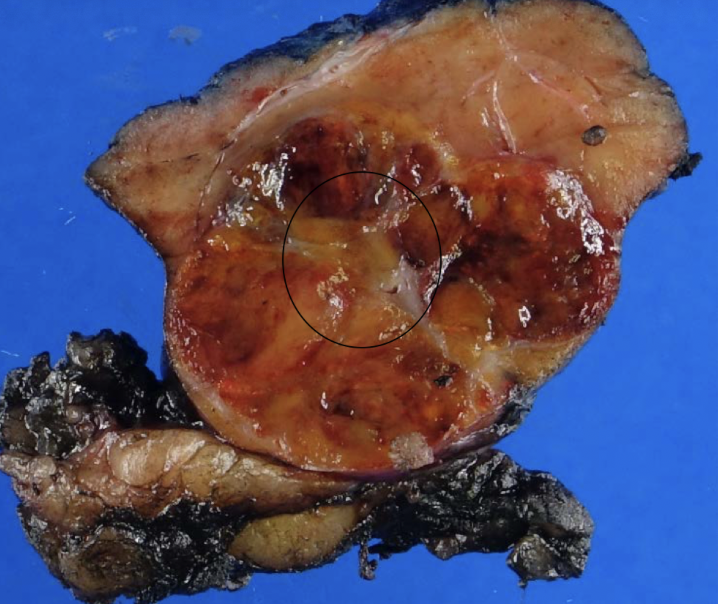

clear cell RCC

most common RCC

arise from proximal tubular epithelium

tendency to invade renal vein

von hippel-lindau syndrome (VHL)

buzzword: high HIF-1, increase VEGF and IGF-1

clear cell RCC

clear cell RCC

glycogen and lipid cytoplasm with rich vascular network

clear cell RCC

RCC type: -3p VHL